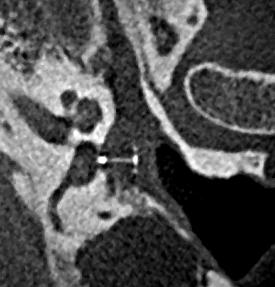

Ambossarrosion mit Stapesprothese Stapesprothese Teflon (Causse) PORP auf Stapes PORP Titan auf Stapes PORP PORP Titan disloziiert Otosklerose Otoskleroseherd TORP Pauke nicht belüftet TORP unter Knorpelinsel disl.